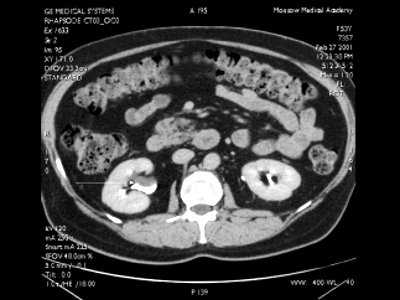

Всего обследовано 64 пациента в возрасте от 21 до 61 года. Интрауретральная ультрасонография выполнена у 21 пациента. У 19 были стриктуры уретры различной локализации, у 1 - склероз шейки мочевого пузыря. Одному больному исследование проведено для исключения рецидива рака после радикальной простатэктомии. Сочетание стриктуры уретры и гиперплазии простаты имело место у 3 пациентов. У 43 больных исследовали верхние мочевые пути (мочеточник, чашечно-лоханочную систему). Из них 33 пациента с обструктивными заболеваниями: 3 - со стриктурами средней и нижней трети мочеточника, 30 - со стенозом лоханочно-мочеточникового сегмента. У 10 пациентов показанием к интрауретеральной ультрасонографии было подозрение на папиллярные образования чашечно-лоханочной системы и (или) мочеточника. Всем больным выполняли общее ультразвуковое исследование, компьютерную томографию, магнитно-резонансную урографию, экскреторную рентгеновскую урографию, ретроградную уретеропиелографию и эндоскопические исследования.

Из 10 обследованных пациентов с подозрением на папиллярные образования чашечно-лоханочной системы и мочеточника, у 8 диагноз не подтвердился. У 1 больного с помощью интрапельвикального эхосканирования была выявлена небольших размеров (0,7 см в диаметре) парапельвикальная киста, создающая дефект наполнения при экскреторной урографии, ретроградной уретеропиелографии, компьютерной томографии с контрастированием (рис. 10).

Рис. 10. КТ органов забрюшинного пространства с контрастированием - дефект наполнения лоханки.